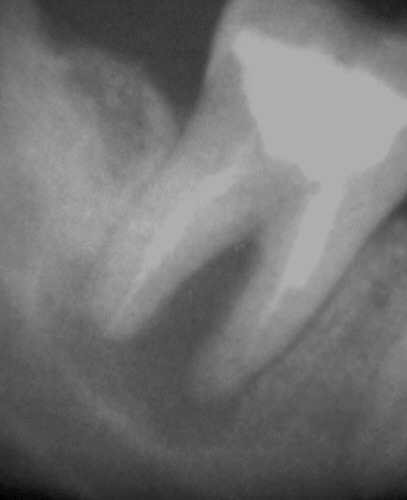

Interessant an dem folgenden Fall ist wiederum, dass die mesialen Kanäle bei der Revision nicht durchgängig waren. Nichtsdestotrotz ist der periapikale Prozess auch an dieser Wurzelspitze röntgenologisch und klinisch vollständig ausgeheilt. CHKM ist ganz offensichtlich ungemein kriechfähig.